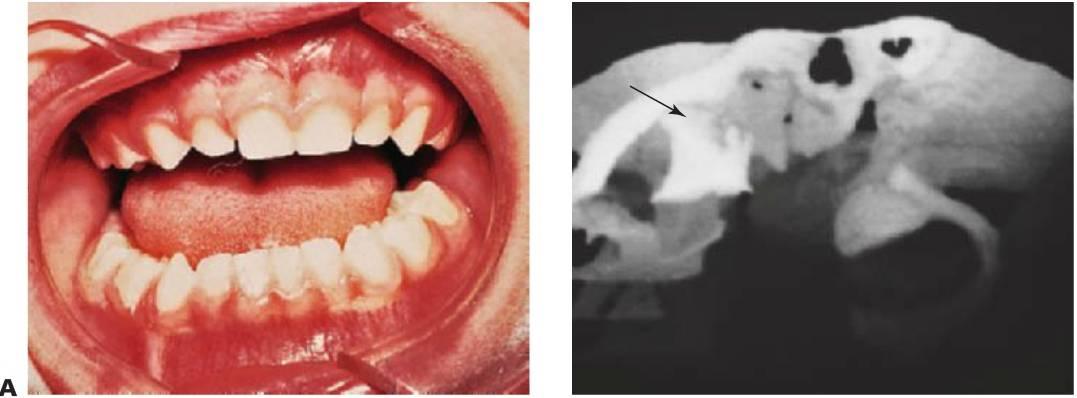

Las fracturas de los huesos faciales no son habituales en niños y representan menos del 5% del total de las fracturas maxilofaciales. En consecuencia, pocos cirujanos presentan una vasta experiencia en esta área, si bien el enfoque que hagan de estos casos deberá valorar las implicaciones de dichas lesiones en el crecimiento del niño (fig. 7.7).

El tratamiento de los traumatismos maxilofaciales en un niño es complicado debido a la presencia de dentición que no ha erupcionado, a la ansiedad, a las consideraciones derivadas del crecimiento y, por último, a la asociación habitual de traumatismos craneales cerrados que pueden retrasar el tratamiento completo. El uso de fijaciones internas como miniplacas y tornillos debe hacerse con cautela para no perjudicar el desarrollo de los gérmenes dentarios y la fijación intermaxilar; con la posible combinación con alambres transóseos, es bien tolerada por los niños. Se pueden utilizar las barras de arco como fijación dental, pero las férulas de plata sobrepuestas son las que se utilizan con más frecuencia de una forma eficaz. Con una adecuada reducción, fijación e inmovilización, así como un tratamiento antibiótico profiláctico y un estricto cuidado oral, las fracturas se unen en 3 semanas. No existe apenas constancia de la no unión o la unión fibrosa.

Debido a que el cuello del cóndilo es relativamente más ancho en los niños y tiene un volumen mayor de hueso esponjoso, las fracturas de la superficie articular son más habituales que en los adultos. En los casos de fractura intracapsular (figs. 7.5, 7.9), el seguimiento durante años permite detectar cualquier alteración de su crecimiento, y en los casos en que aparezca una limitación de la apertura o una anquilosis franca, se recomienda una intervención temprana con un injerto costocondral.